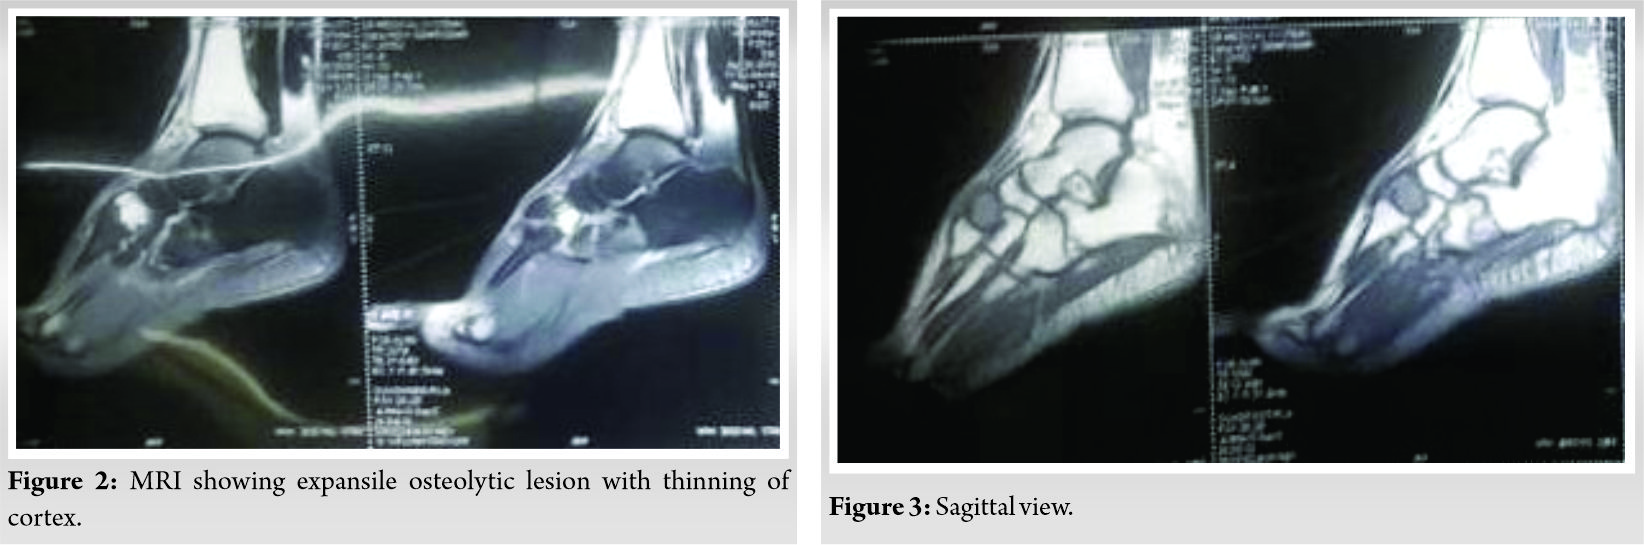

MRI of right foot (Fig. 2, 3, 4, 7) was done which showed an expansile osteolytic lesion with multiple internal septations in intermediate cuneiform with thinning of the cortex.

In radiology, it is difficult to differentiate between GCT and ABC. Because both will have osteolytic lesion in X-ray [4]. MRI will show hyperintense lesion in T2 MRI and hypo-intense lesion in T1 MRI. MRI will show fluid-filled levels in ABC, but it is not typical to ABC. This finding can also be seen in other GCT like lesions such as chondroblastoma [12].

Hence, only histology can differentiate between primary ABC and secondary ABC evolving from GCT. In our case, there were no septations seen in the lesion as per X-ray. In MRI, there were no fluid levels. Hence, our diagnosis before biopsy report was provisionally made as GCT. However, biopsy report showed the presence of hemorrhagic areas, and hence, it was diagnosed as GCT transforming into ABC. However, the treatment will not vary for both the conditions unless any features of malignant changes are present in the biopsy.